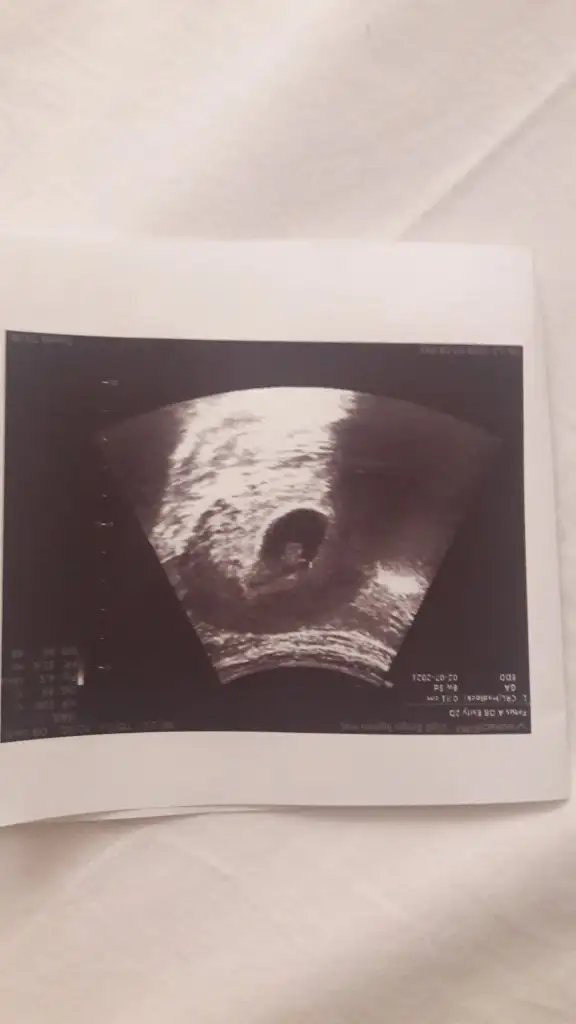

Kese olayı tamamiyle yanlış. Benim birisi yuvarlak birisi uzun muz gibiydi.(ikiz) Biri kız biri oğlan olur diyordum. En başından beri öyleydi. Ama yok kesin ikisi de kızmış :)

Ay ne kadar tatlış maşallah nasılda durmuş tüm resimlere baktım da bu dikkatimi çekti çok güzel durmuş minnacık Allah hayırlısıyla kucağına almayı nasip etsinMeraba arkadaslar benimki içinde tahminde bulunursaniz çok sevinirim 10 haftalik![]()

Erkek gibi geldi bana sizinkiKızlar 6+4 teki ultrason kağıdım kese bildiğin armut gibiydiYorumlayacak olan varmı?

Karından mı canımKizlar banada yorum yaparmisiniz rica etsem6+4 burda

Amin insallah hayırlı bi sekilde canımAmin canım Rabbim sağlıklı hayırlı birer oğluş nasip etsin inşallah bize![]()